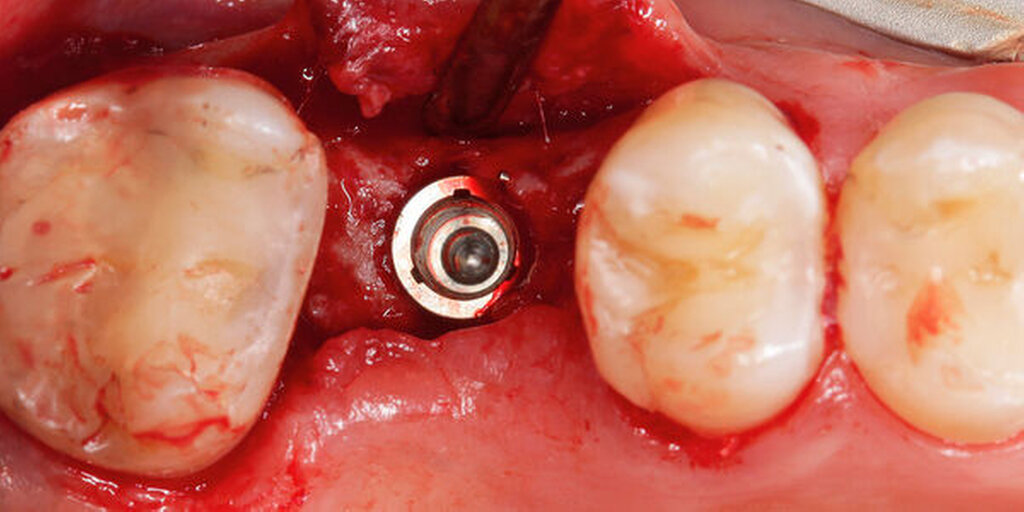

Im vorliegenden Patientenfall wurde die Implantation statisch navigiert mithilfe einer Bohrschablone und einer voll geführten Insertion durchgeführt (Abbildung 3). Dafür wurde der STL-Datensatz der Bohrschablone nach der Konstruktion in der IPS durch einen spezialisierten Mitarbeiter des Servicepartners DEDICAM (CAMLOG Vertriebs GmbH, Wimsheim) für die Bohrschablone zur Verfügung gestellt. Die Herstellung der Schablone erfolgte mithilfe eines 3-D-Druckers (Form 3, Formlabs GmbH, Berlin) im zahntechnischen Labor der Charité – Universitätsmedizin Berlin. Alternativ hierzu kann die Schablone auch vollständig fertig gestellt beim entsprechenden Anbieter bestellt werden.

Die genaue Gestaltung der Bohrschablone ist abhängig vom Bohrprotokoll und der Führungsmethode des jeweiligen Implantatherstellers. Beim vorliegenden Patientenfall und Implantatsystem fanden die Aufbereitung des Implantatbetts und die Implantatinsertion durch eine in die Schablone eingeklebte Metallhülse statt (Abbildungen 4 und 5). Sowohl die Bohrer als auch die Einbringpfosten erreichen dabei einen definierten Tiefenstopp (Abbildung 4).